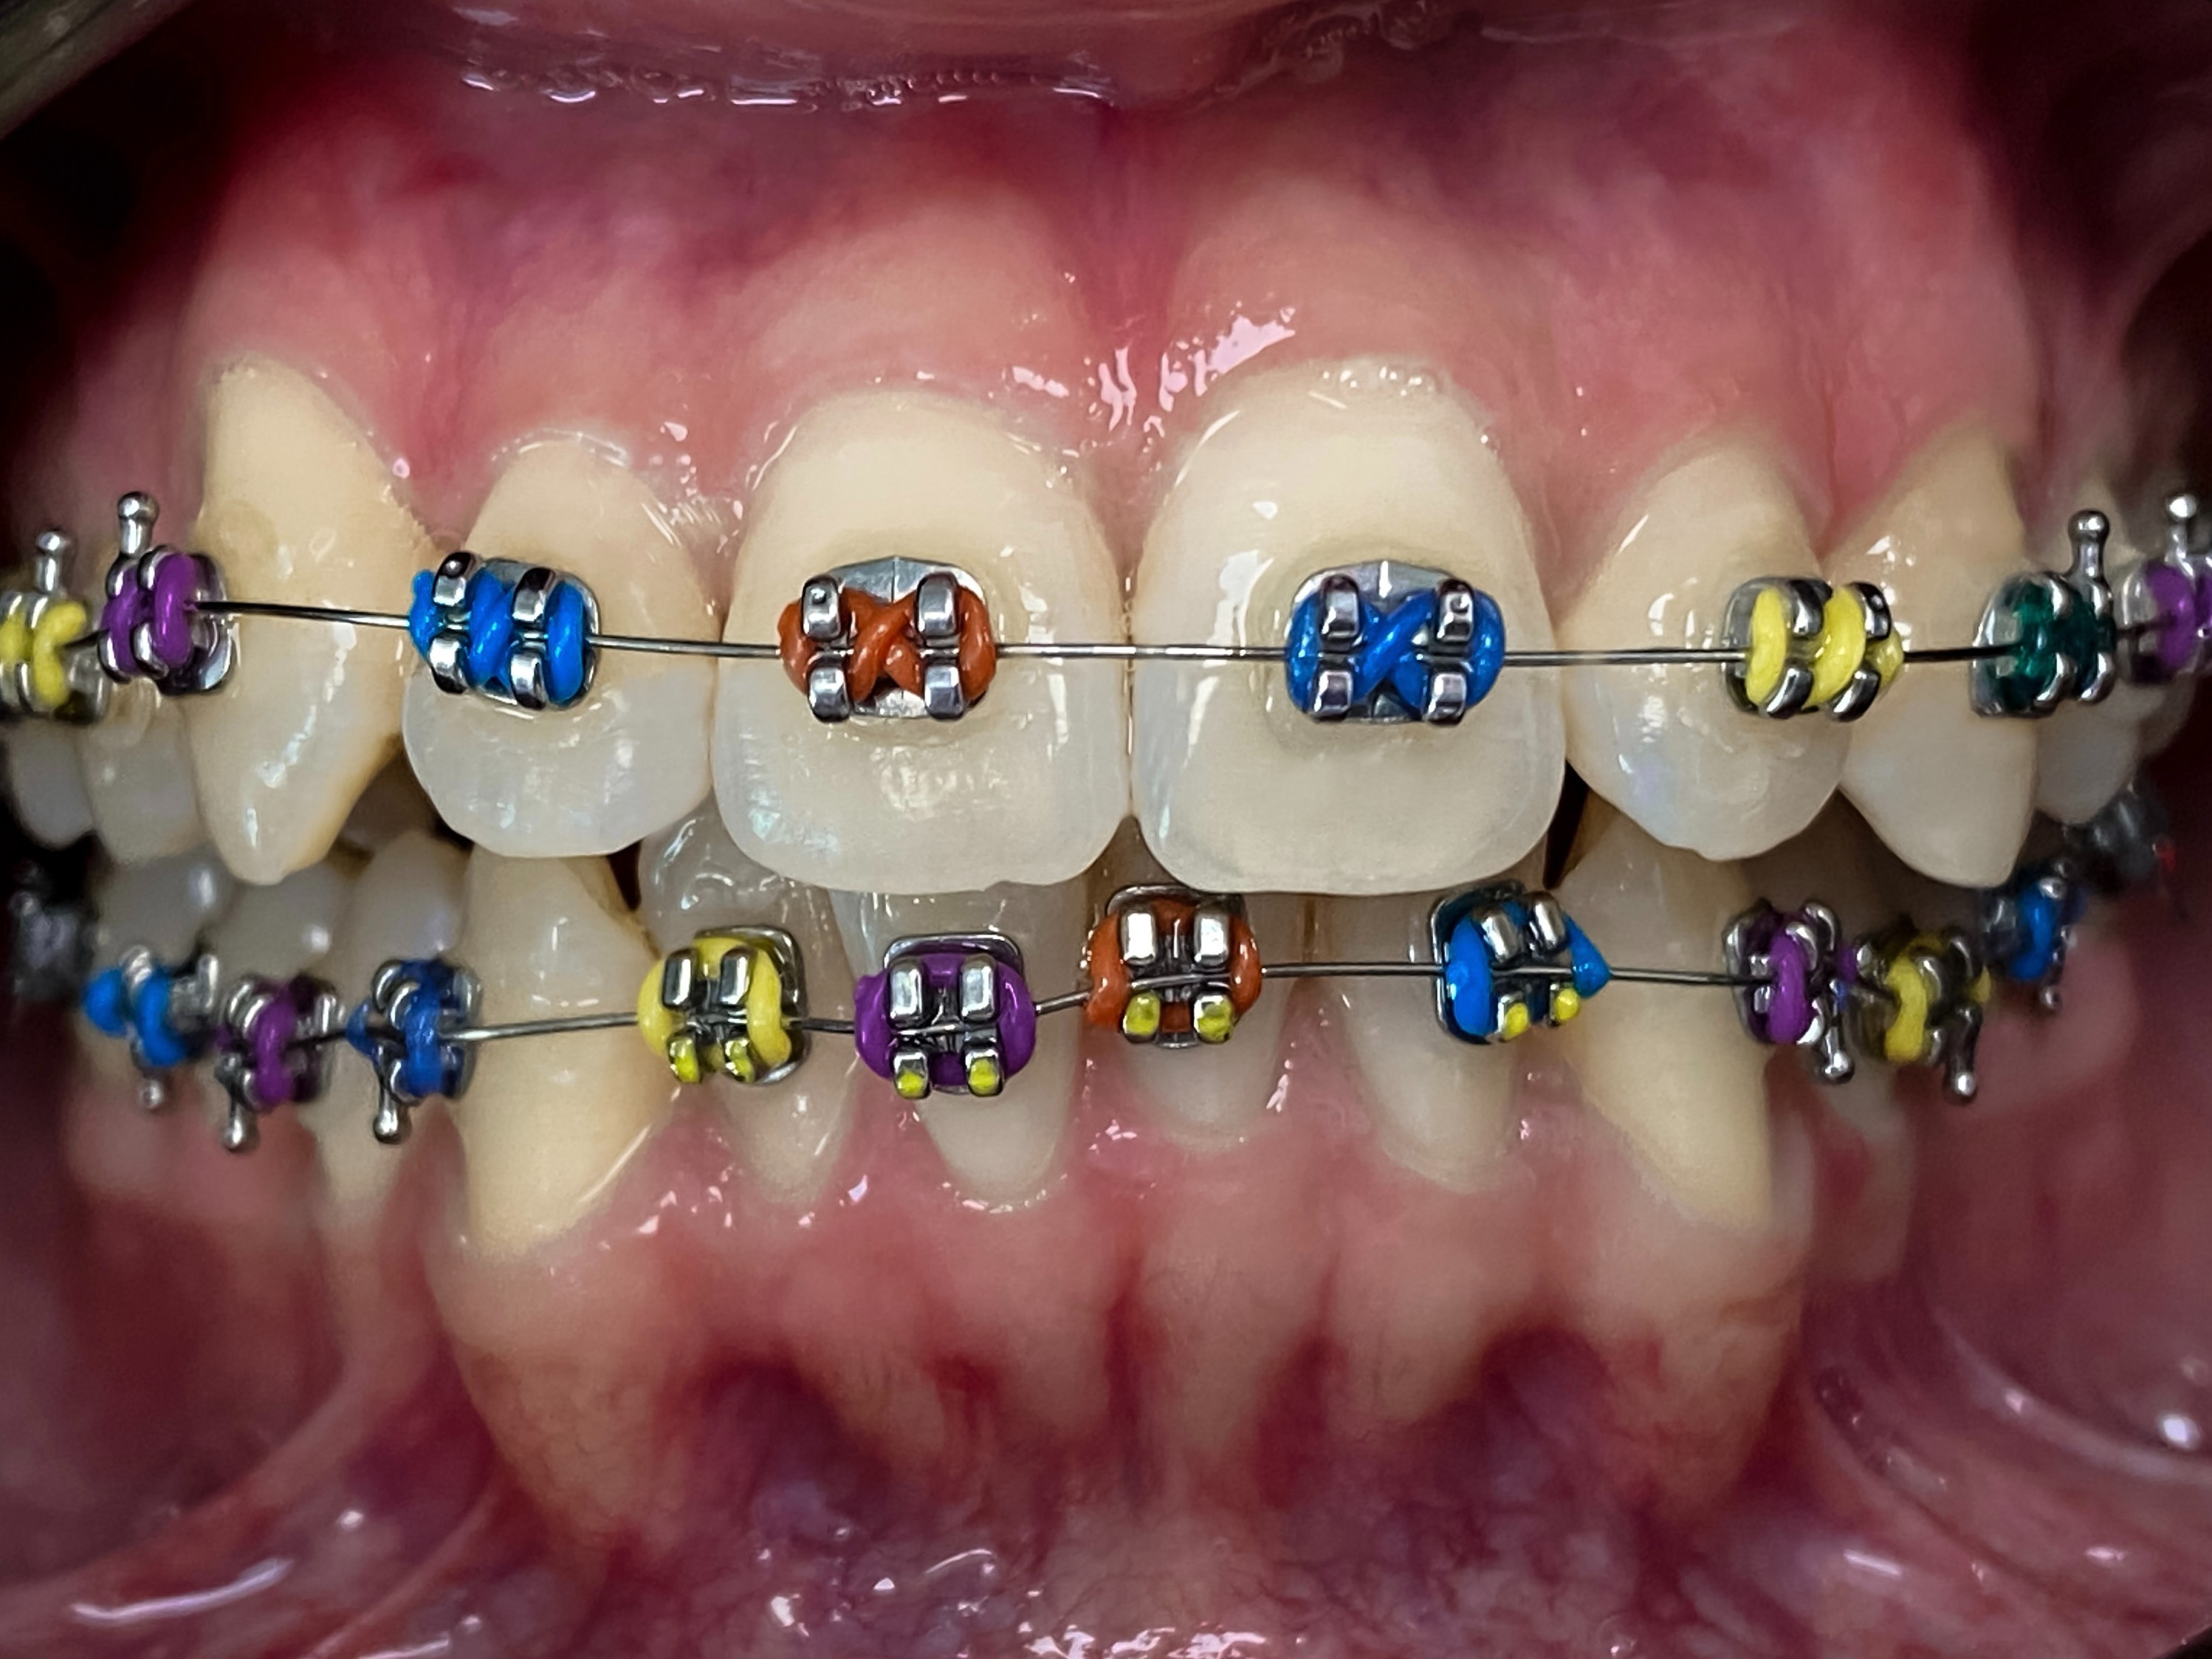

Ортодонтична терапія

Ортодонтичне здоров'я - це важлива складова здоров'я ротової порожнини та здоров'я в цілому. Ортодонтична терапія - це естетика, функціональність та психічне благополуччя.